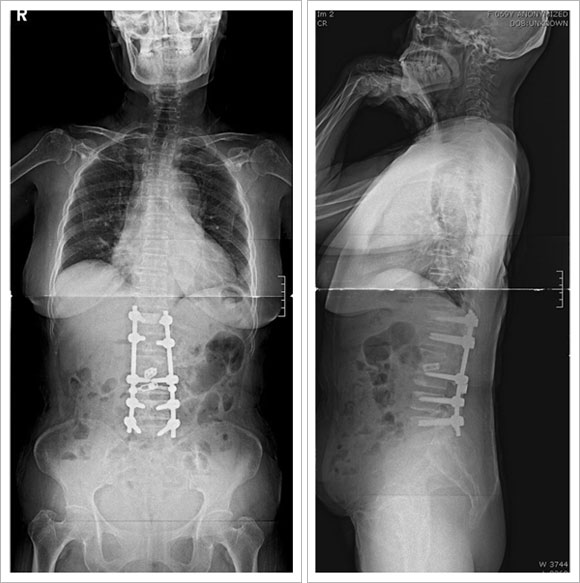

¼ö¼úÀû Ä¡·á

- ¼ºÀå±âÀÇ

45µµ ÀÌ»óÀÇ ¸¸°î

- ¼ºÀåÀÌ ³¡³ 50µµ ÀÌ»óÀÇ ¸¸°î

* ¼ö¼ú¹ý

- ÈĹ汳Á¤ ¹× ÈĹæ±â±â¼ú : ôÃß°æ ³ª»ç¸ø

°íÁ¤¼ú

- Àü¹æ±³Á¤ ¹× Àü¹æ±â±â¼ú : ÃÖ¼ÒÀý°³¹æ½Ä,

³»½Ã°æ ¹æ¹ý

- ÀüÈĹ汳Á¤ ¹× ÈĹæ±â±â¼ú

- °ßÀÎ ÈÄ ÈĹ汳Á¤¼ú

- Èä°û¼ºÇü¼ú

û¼Ò³â±â Ư¹ß¼º ôÃßÃø¸¸Áõ : 20¼¼/¿©ÀÚ

2) ÅðÇ༺ ôÃßÃø¸¸Áõ

: 78¼¼/¿©ÀÚ

| |

ÁÖ·Î ³ªÀ̰¡

µé¸é¼ ¹ß»ýµÇ¸ç ôÃß°ü ÇùÂøÁõÀÌ ÁÖÁõ»ó

Ä¡·á´Â ôÃß°ü ÇùÂøÁõ¿¡ ´ëÇÑ Ä¡·á¿Í º¯Çü±³Á¤À» µ¿½Ã¿¡ ½Ç½ÃÇÔ